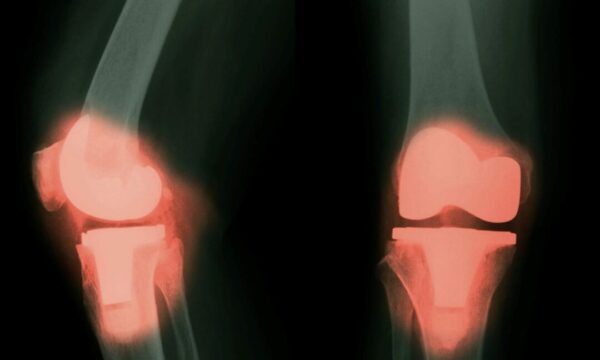

人工関節からの金属が血液と脳に入る可能性=研究